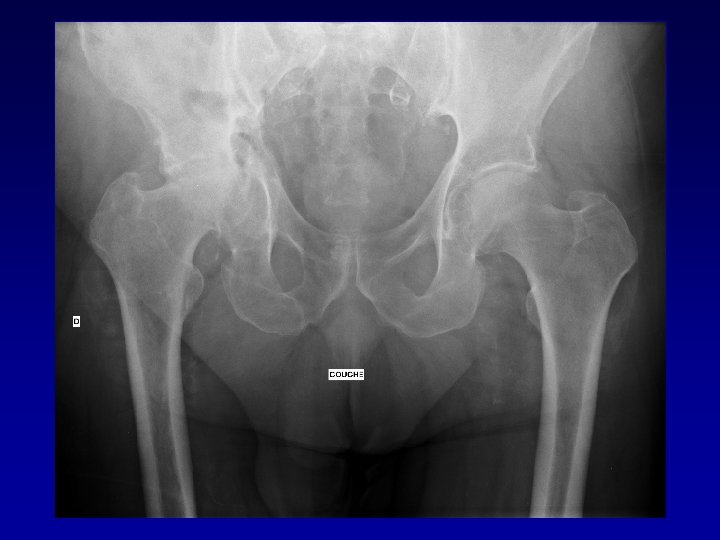

Déformation du cotyle • Ascensionné • Perte de substance osseuse scanner • Pseudarthrose •

Déformation du cotyle • Ascensionné • Perte de substance osseuse scanner • Pseudarthrose • Perte du positionnement exact (idem LCH) • Doit être reconstruit et recentré

Après bilan • Coxarthrose banale Arthroplastie totale habituelle • Coxarthrose spécifique Arthroplastie difficile